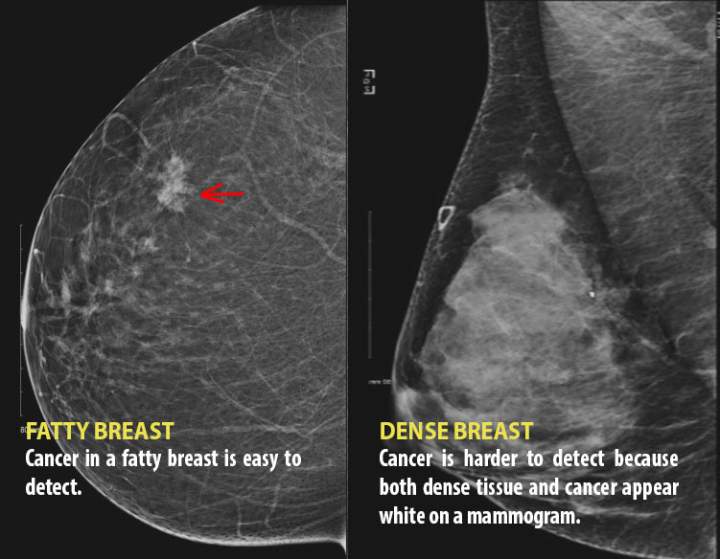

Many women aren’t told they have dense breasts. Here’s why it matters43 per cent of women ages 40 to 74 have dense breasts, and they can have serious implications.LifestyleOct 3, 2019

We need to talk about dense breasts: Why governments are taking noticeDetecting cancer in a dense breast with a mammogram is "kind of like seeing a snowball in it in a snowstorm."CanadaSep 23, 2018